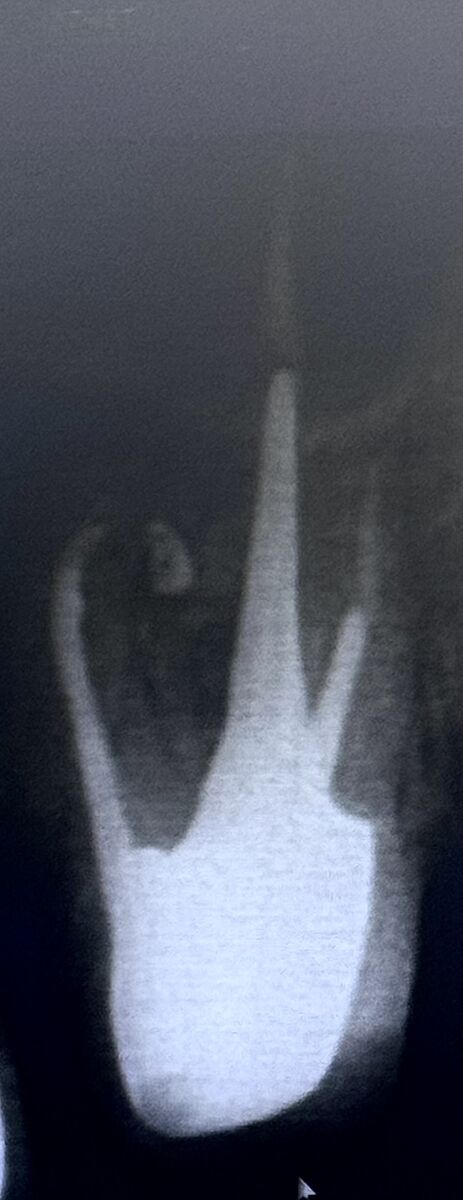

2.6 зуб: 3 кореня 4 канали (MB2); нерентгенконтрастна ортопедична конструкція, вкладка. Стан

ендодонтичного лікування: пломбувальний матеріал у каналі

простежується гомогенно, до верхівки, у каналах щічних коренів -гомогенно, не до верхівок. У верхівковій третині щічно-мезіального кореня визначається вогнище деструкції кісткової

овальної форми, неоднорідної структури (за рахунок фрагменту виведеної

пломбувальної маси), з чіткими, рівними межами, обідком остеосклерозу по периферії. розміром 3,65×5,5×4,05 мм (акс. *кор.* саг